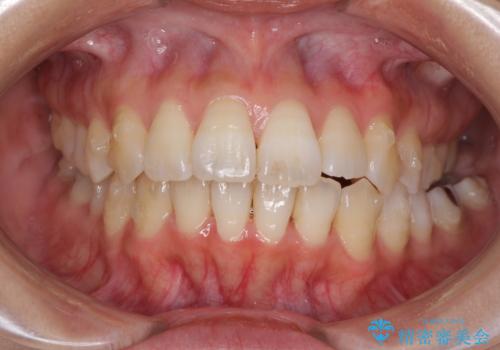

- 上下の歯の前後関係が乱れ、歯に負担がかかるとのことで来院された患者様です。

下顎が右左側に変位しているため、左側奥歯の咬み合わせが上下反対の関係となっていました。

また、上下ともに歯列が狭窄しており、奥歯以外にも反対咬合が認められました。